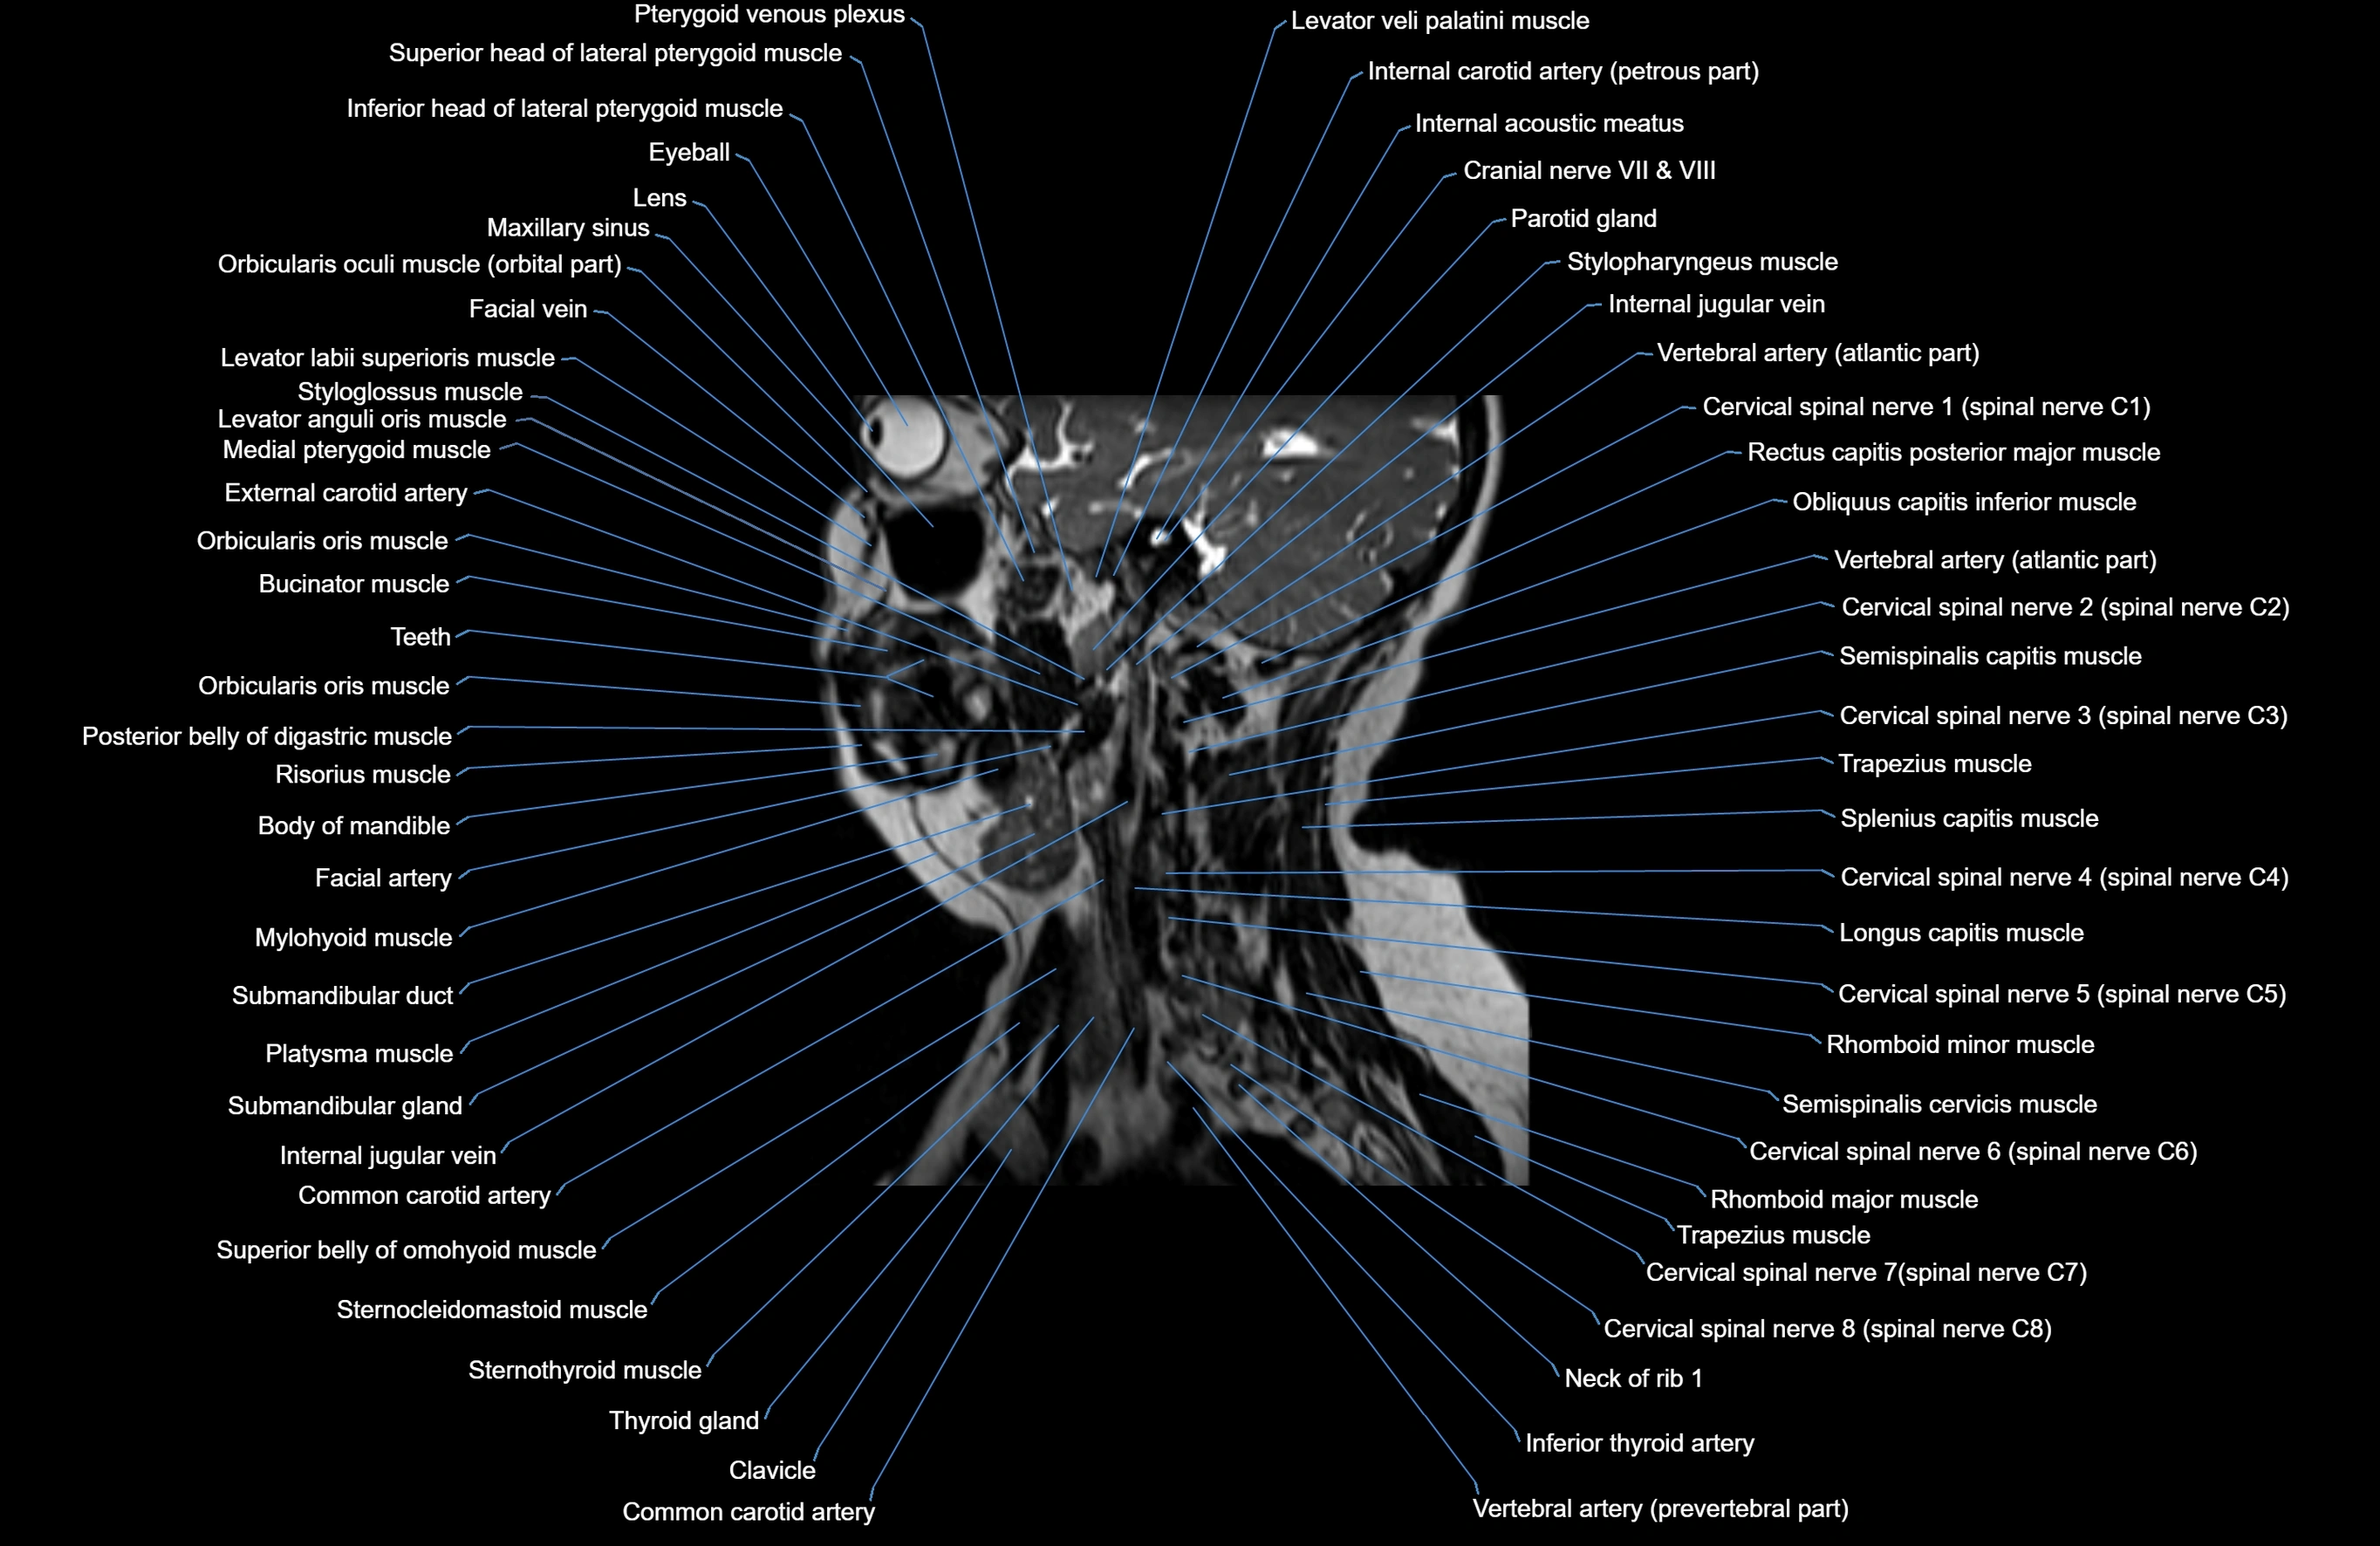

- Cervical spinal nerve 1 (C1)

- Cervical spinal nerve 2 (C2)

- Cervical spinal nerve 3 (C3)

- Cervical spinal nerve 4 (C4)

- Cervical spinal nerve 5 (C5)

- Cervical spinal nerve 6 (C6)

- Cervical spinal nerve 7 (C7)

- Cervical spinal nerve 8 (C8)

- Clavicle

- Common carotid artery

- Inferior thyroid artery

- Internal carotid artery (petrous part)

- Levator veli palatini muscle

- Medial pterygoid muscle

- Mylohyoid muscle

- Platysma muscle

- Rhomboid major muscle

- Rhomboid minor muscle

- Semispinalis capitis muscle

- Semispinalis cervicis muscle

- Splenius capitis muscle

- Sternocleidomastoid muscle

- Sternothyroid muscle

- Submandibular gland

- Superior belly of omohyoid muscle

- Thyroid gland